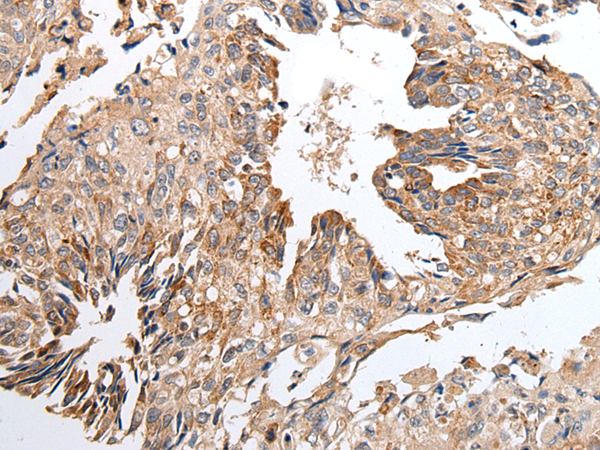

IHC positive control: |

Human lung cancer and human breast cancer |

IHC Recommend dilution: |

25-100 |